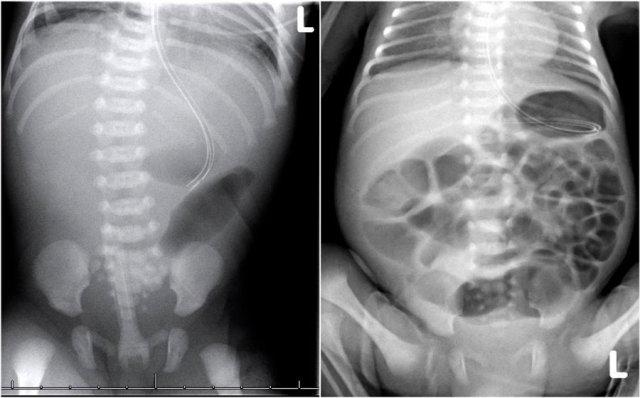

Ca lâm sàng 3

Quan sát hình ảnh.

Mô tả các dấu hiệu và đưa ra chẩn đoán của bạn.

Sau đó cuộn qua các hình ảnh để xem chẩn đoán.

Các dấu hiệu bao gồm:

- Nhiều quai ruột non giãn cho thấy tắc nghẽn đoạn thấp

- Thụt tháo cản quang cho thấy khẩu kính nhỏ ở trực tràng, đại tràng sigma và đại tràng xuống

Chẩn đoán:

Bệnh Hirschsprung đoạn dài

Ca lâm sàng 4

- Nhiều quai ruột non giãn

- Khí trong thành ruột (Pneumatosis intestinalis).

- Tràn khí ổ bụng (Pneumoperitoneum).

Viêm ruột hoại tử (NEC) có thủng ruột.